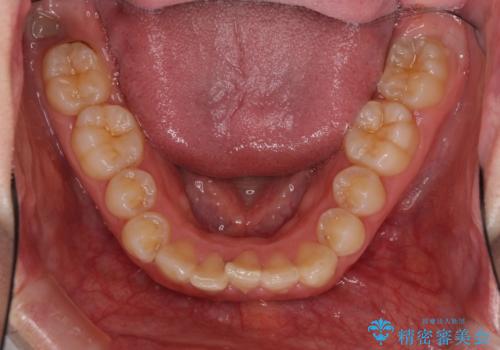

- 八重歯を気にして来院された患者様です。

八重歯の後ろの歯を1歯抜歯し、補助装置(リンガルアーチ)を用いて八重歯の位置を改善し、その後インビザラインにより矯正治療を行うこととしました。

下顎前歯が1本欠損したスリーインサイザーという状態であるため、上下の前歯の咬み込みが深くなったり、奥歯の咬み合わせが理想的なものとならなかったりという仕上がりになってしまいます。

前歯の見た目や奥歯の咬み合わせに、患者様が違和感を感じない状態として治療を終えました。